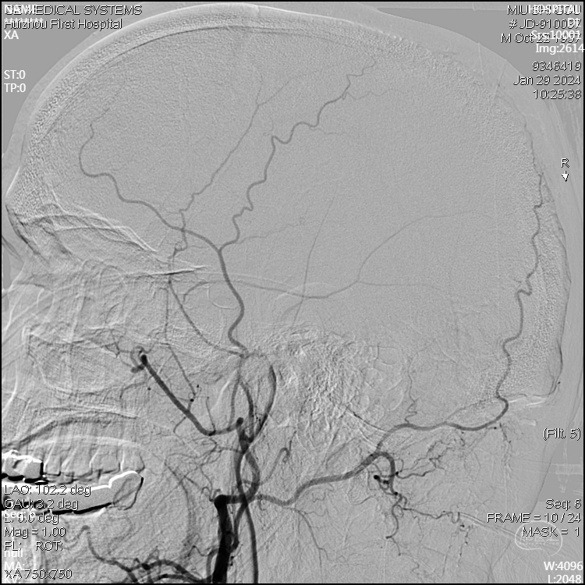

急诊DSA未见畸形血管。

右侧颈外侧位